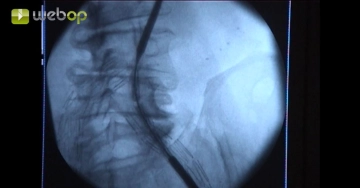

In this case, exposure of the left groin was preferred over puncture because of severe scarring in the groin after previous surgery and the large caliber of the delivery system. After encircling the common femoral artery centrad and distad, puncture the artery in Seldinger technique. Introduce a 7 F sheath over the guidewire. Administer 5000 IU heparin saline locally into the vessel.

To avoid vessel perforation, do not advance the stiff guidewire too far because of the severe kinking of the left iliac arteries and the paper-thin vessel walls.